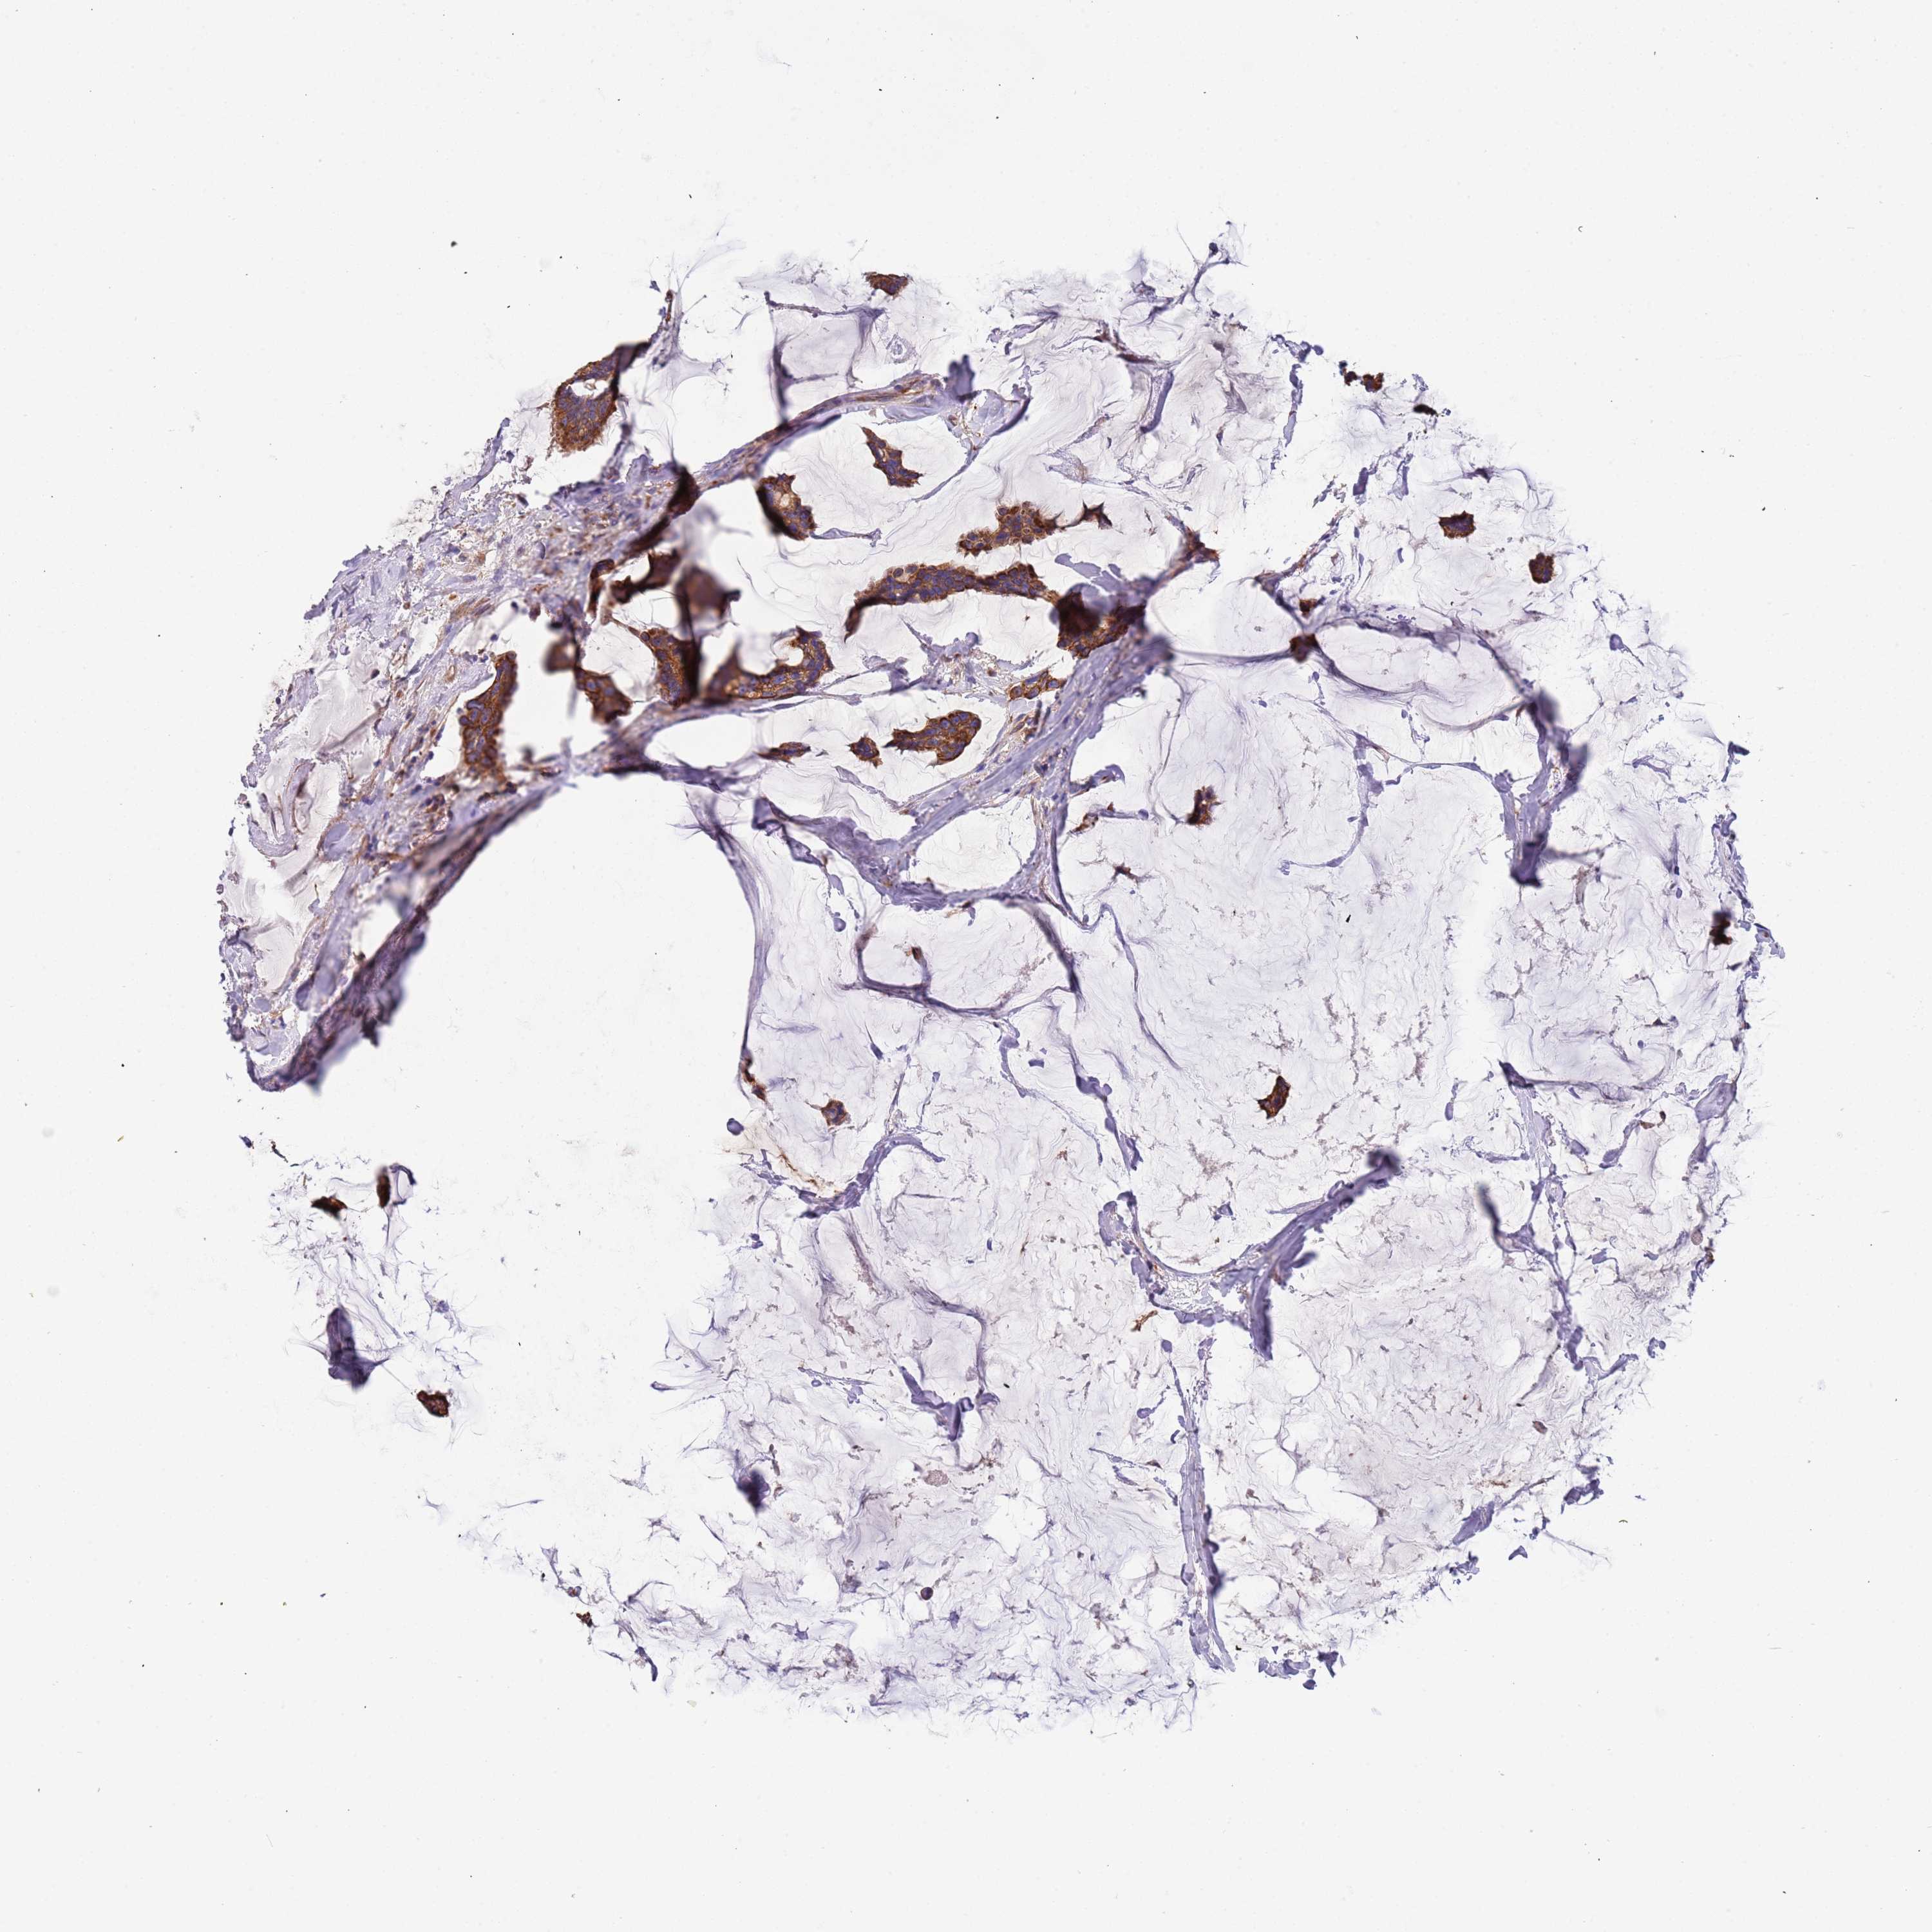

CANCER BREAST CANCER Show tissue menu

BRCA TCGA BRCA VALIDATION PROTEIN EXPRESSION

ANTIBODIES

AND

VALIDATION